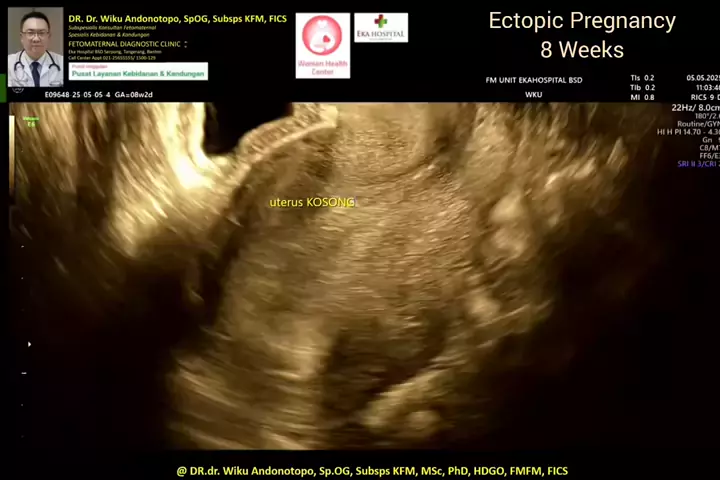

Ectopic Pregnancy 8 weeks.. #skriningkehamilan #drwikuandonotopo #drwiku_andonotopo #polikandunganekahospitalbsd #ekahospitalbsd #ekahospitalcibubur #ekahospitalpekanbaru #ekahospitalbekasi #rsiafamilypluit #grandfamilypik #usgkehamilansehat #usgkehamilan #usg4d #usg4dimensi #fetomaternal #usgfetomaternal #konsultanfetomaternal #fetomaternalpontianak #fetomaternalekahospitalbsd #fetomaternaljakarta #fetomaternalserpong #fetomaternaltangerang #fetomaternalmedan #fetomaternalpalembang #fetomatern...